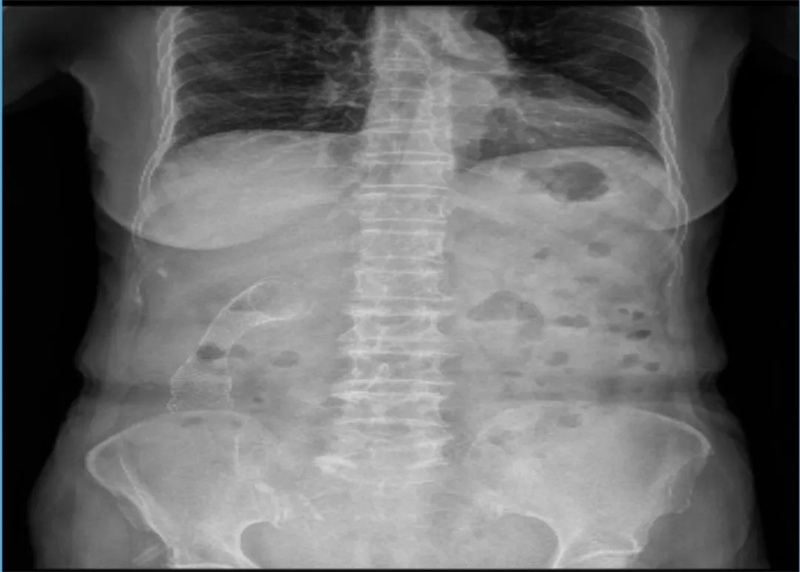

郭奶奶(化名)因持续腹胀、腹痛并伴恶心来到池州市第二人民医院急诊科就诊。经腹部CT检查,提示腹水、结肠壁增厚,考虑结肠肿瘤,并伴有肝、脾低密度灶及肝右叶外缘结节、腹膜后及大网膜多发结节,转移待排。普外二科团队联合会诊后,确诊为晚期升结肠癌伴肠梗阻。